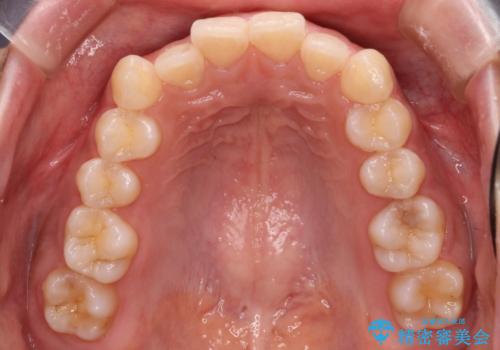

犬歯のねじれ 下の歯のがたがた インビザラインで

- 右上の犬歯のねじれ、下の歯のがたつきを主訴に来院。

インビザラインで歯を抜かずに並べました。

初回:上顎16ステージ 下顎22ステージ

リファインメント: 上顎23ステージ 下顎20ステージ